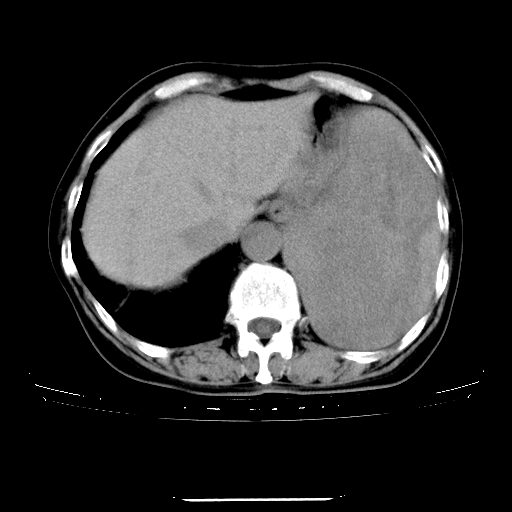

女,75岁,咳嗽、咳痰一周,无咯血,低热两天。

脾脏明显增大,其内可见低密度灶,边界不清。考虑占位性病变。

首先考虑为脾脏明显肿大,内可见多量弥漫性低密度区,边界不清,考虑脾占位性病变,以转移瘤及淋巴瘤可能性大.

其次考虑肺内病灶如恶性肺间质肉瘤,建议增强及胸腹部扫描

巨大脾脏向上突入胸腔,脾实质密度不均匀,内见低密度影。

结合发热病史考虑巨脾合并坏死。

建议增强扫描。

导致巨脾原因:血液系统病变(慢粒)?淋巴管瘤?恶性组织细胞增生症?建议临床进一步检查。